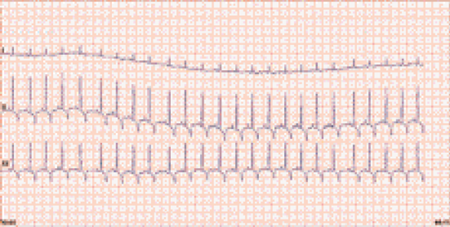

- Le système sympathique est cardio stimulateur, médié par les catécholamines, adrénaline et noradrénaline. Dans des conditions normales, l’augmentation du tonus sympathique entraîne une tachycardie sinusale (photo 1), une augmentation de l’excitabilité et un raccourcissement de l’intervalle P-Q.

Photo 1 : Tachycardie sinusale physiologique (photos E. Bomassi)